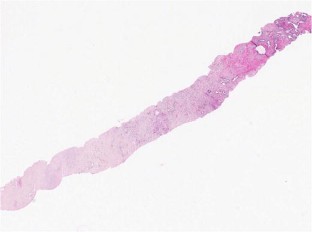

Low-risk prostate adenocarcinoma is classically managed either with active surveillance or radical therapy (such as external radiotherapy or radical prostatectomy), but both have significant side effects. Vascular-targeted photodynamic therapy (VTP) is a focal therapy proposed as an alternative approach for localized, low-volume, and low-Gleason score (≤6) carcinomas. We report histological modifications observed in prostate biopsies of 56 patients, performed 6 months after VTP using the photosensitizer TOOKAD® Soluble (WST11) and low-energy laser administered in the tumor area transperineally by optic fibers. In 53 patients, we observed sharply demarcated hyaline fibrotic scars, with or without rare atrophic glands, sometimes reduced to corpora amylacea surrounded by giant multinuclear macrophages. Mild chronic inflammation, hemosiderin, and coagulative necrosis were also observed. When residual cancer was present in a treated lobe (17 patients), it was always located outside the scar, most often close to the prostate capsule, and it showed no therapy-related modification. Histopathological interpretation of post-WST11 VTP prostate biopsies was straightforward, in contrast with that of prostate biopsies after radio or hormonal therapy, which introduces lesions difficult to interpret. VTP resulted in complete ablation of cancer in the targeted area.